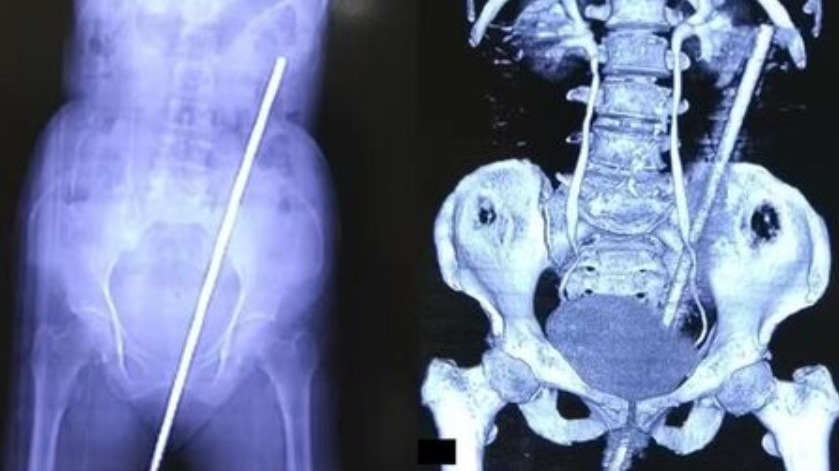

O incidente ocorreu quando a mulher escorregou em um campo próximo à sua casa e caiu sobre a barra de metal, que estava parcialmente enterrada no solo